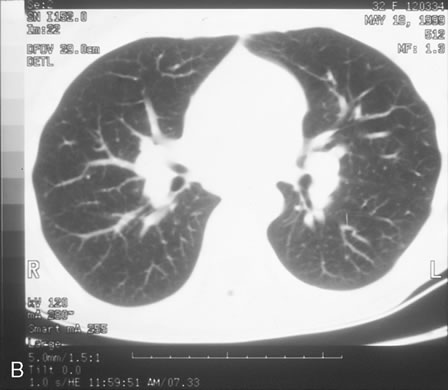

Mycobacterium tuberculosis is a bacterium that causes infection through inhalation of aerosolized droplets filled with the organism. An asymptomatic pulmonary granuloma may develop and reactivate at any point, particularly when accompanied by diseases such as HIV, malignancy, and diabetes mellitus. Rates of reactivity have been found to be highest in non-white, older men of lower socioeconomic status. In the last decade a resurgence of tuberculosis (TB), particularly in crowded urban settings such as New York City, has been noted.60

Ocular involvement most commonly occurs after reactivation in the lung or alimentary tract and is thus referred to as secondary TB (Fig. 16). Primary ocular involvement of TB is rare and is almost always limited to the cornea and conjunctiva. Conjunctival TB has been reported as a chronic unilateral conjunctivitis with a conjunctival mass or ulceration associated with regional lymphadenopathy. Although also rarely seen, conjunctival phlyctenulosis has been found to be associated with tuberculoprotein hypersensitivity. Biopsy and culture proven scleral TB was reported in the literature in 1976 and 1989. Other ocular manifestations of TB include anterior uveitis, either granulomatous or nongranulomatous, choroiditis, and choriodal tubercles/tuberculoma. A recent case series demonstrated the protean ocular findings associated with intraocular TB in addition to a variable response to antitubercular treatment.61

The gold standard for diagnosis of intraocular tuberculosis is demonstration of acid-fast bacilli in fluid or tissue sample either by direct smear and culture, polymerase chain reaction (PCR) or ELISA (Fig. 17). A screening test such as the Mantoux test is useful but is less specific and must be interpreted based on the size of induration in correlation with socioeconomic status, immune status, and contact history of the patient. The test consists of an intradermal injection of purified protein derivative (PPD) from tubercle bacilli. Systemic sensitization to this protein occurs several weeks after primary infection. At 48 to 72 hours postinjection, skin induration larger than 5 mm in an HIV-positive patient or patients with a positive chest x-ray that are previously untreated, larger than 10 mm in other high-risk populations, and larger than 15 mm for healthy patients with low risk factors are considered significant. A positive reaction may persist in the absence of clinically active disease and therefore must be correlated with chest radiography and symptomatology.